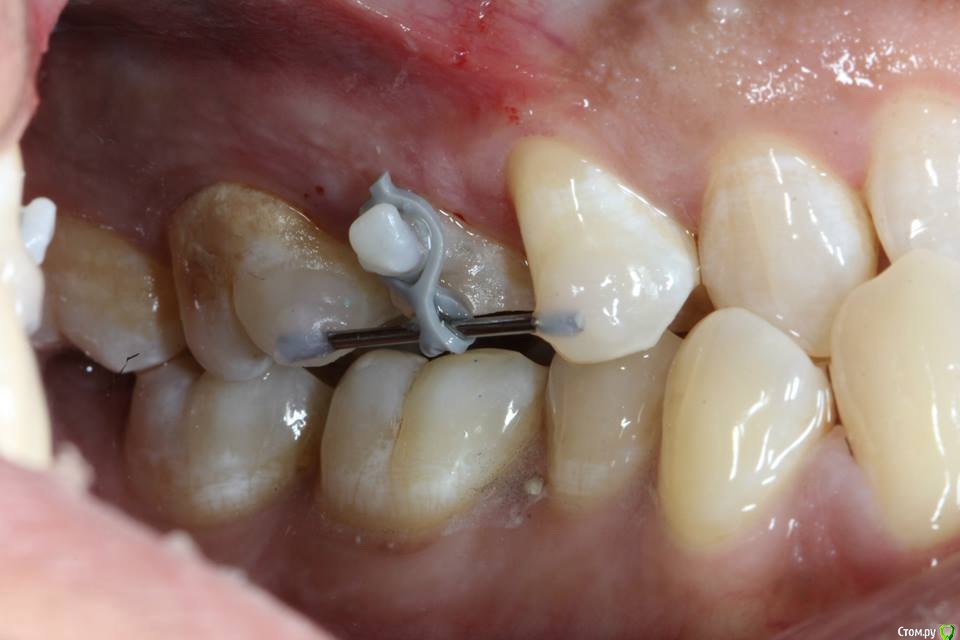

Kolchanov Опубликовано 23 июня, 2015 Поделиться Опубликовано 23 июня, 2015 Экструзия одиночного зуба для получения хоть какого-нибудь феррула. Подозреваю, что процедура не очень сложна и вполне модет быть освоена простым терапевтишкой, т.е. мной. Был бы очень благодарен, если бы кто-нибудь накидал своих мыслей по этому поводу, а еще лучше и фоток. И, конечно же, перечисление материалов. В одной из клиник, где я работаю, делают так иногда.После удаления штифтового зуба имеем поддесневой дефектhttp://s010.radikal.ru/i311/1506/49/4f3a03a5b53b.jpghttp://s010.radikal.ru/i313/1506/55/c752a532f478.jpgПациентка пожелала зуб сохранить. Теперь его тянут. И пятерочку еще в придачу.http://s014.radikal.ru/i327/1506/75/e9897bfb0e24.jpghttp://i024.radikal.ru/1506/99/1f1453b881ef.jpghttp://s017.radikal.ru/i434/1506/ea/caf4284659b4.jpghttp://s018.radikal.ru/i522/1506/ae/b2b54bddcdb8.jpghttp://s015.radikal.ru/i331/1506/7c/0efe752f8c35.jpgПока ничего сложного не вижу.У меня сейчас есть похожий случай. Но, послать в Москву... Не поедут. А на местного ортодонта как-то надежды мало. Я потом залью сюда фотки со своими мыслями. Может кто что присоветует...Спасибо! 1 Ссылка на комментарий

krokomot Опубликовано 23 июня, 2015 Поделиться Опубликовано 23 июня, 2015 Экструзия одиночного зуба для получения хоть какого-нибудь феррула. Подозреваю, что процедура не очень сложна и вполне модет быть освоена простым терапевтишкой, т.е. мной. Был бы очень благодарен, если бы кто-нибудь накидал своих мыслей по этому поводу, а еще лучше и фоток. И, конечно же, перечисление материалов. В одной из клиник, где я работаю, делают так иногда.После удаления штифтового зуба имеем поддесневой дефект Пациентка пожелала зуб сохранить. Теперь его тянут. И пятерочку еще в придачу. Пока ничего сложного не вижу.У меня сейчас есть похожий случай. Но, послать в Москву... Не поедут. А на местного ортодонта как-то надежды мало. Я потом залью сюда фотки со своими мыслями. Может кто что присоветует...Спасибо!Ох и любят у нас врачи заниматься вот таким лепиловом)))) Инженера в себе не скроешь)) Почему не с бреккетами? Приклеили несколько, дугу, цепочку проволку, что угодно, все же проще и предсказуемее (и быстрее) Ссылка на комментарий